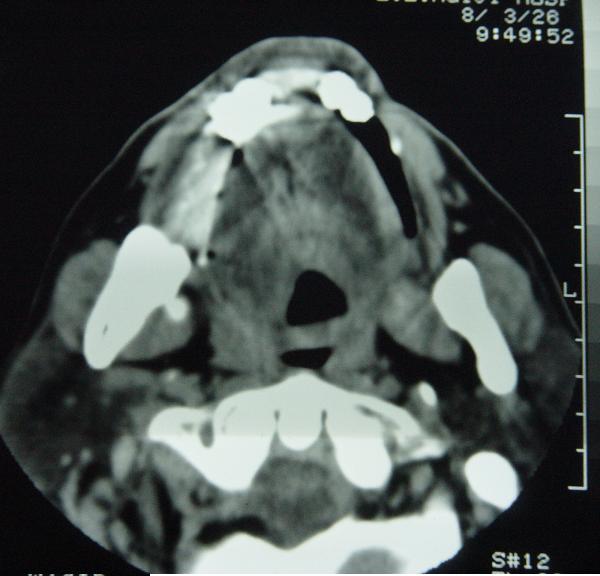

标题: CT12465:下颌骨肿瘤,请会诊 [打印本页]

标题: CT12465:下颌骨肿瘤,请会诊

发现下颌骨肿瘤近30年.逐渐增大.

考虑右侧下颌骨水平部及升部骨纤维异常增殖症可能性大。

造釉细胞瘤,没有特征性;半月切迹?骨间隔?多房性骨密度减低区,大小不等。鉴别;动脉瘤样骨囊肿,骨软骨瘤。本人,更倾向于---骨软骨瘤。

考虑右侧下颌骨骨化性纤维瘤。